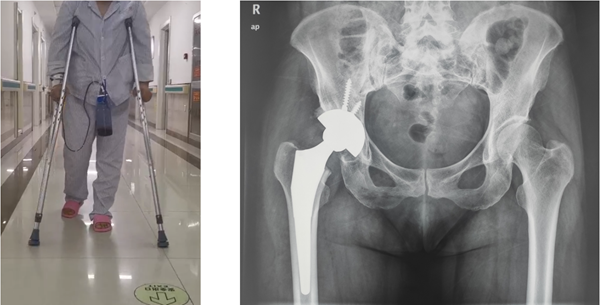

经过周密的术前规划,刘阿姨的手术过程非常顺利,手术仅1个多小时便成功完成。术中实际使用假体型号与术前规划结果一致,刘阿姨对手术非常满意。

在微创髋关节置换理念的指导下,术后6小时刘阿姨就正常下地行走,活动自如。术后X光片显示,假体位置良好,恢复了生理解剖。